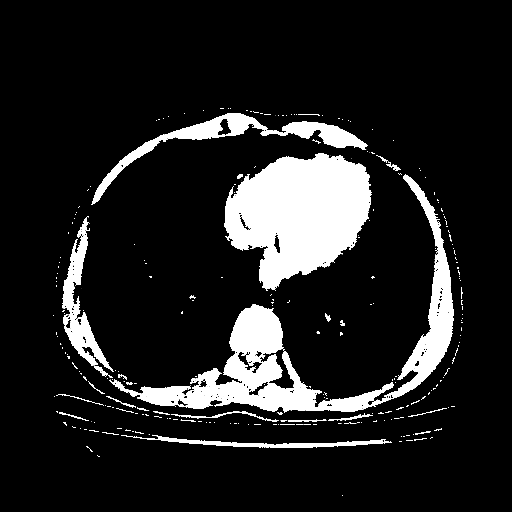

Original VENOUS CT scan

Full window (WL 1023.5, WW 4095 β†’ Low βˆ’1024, High +3071)

Actual HU range: [-1024.0, 3071.0]